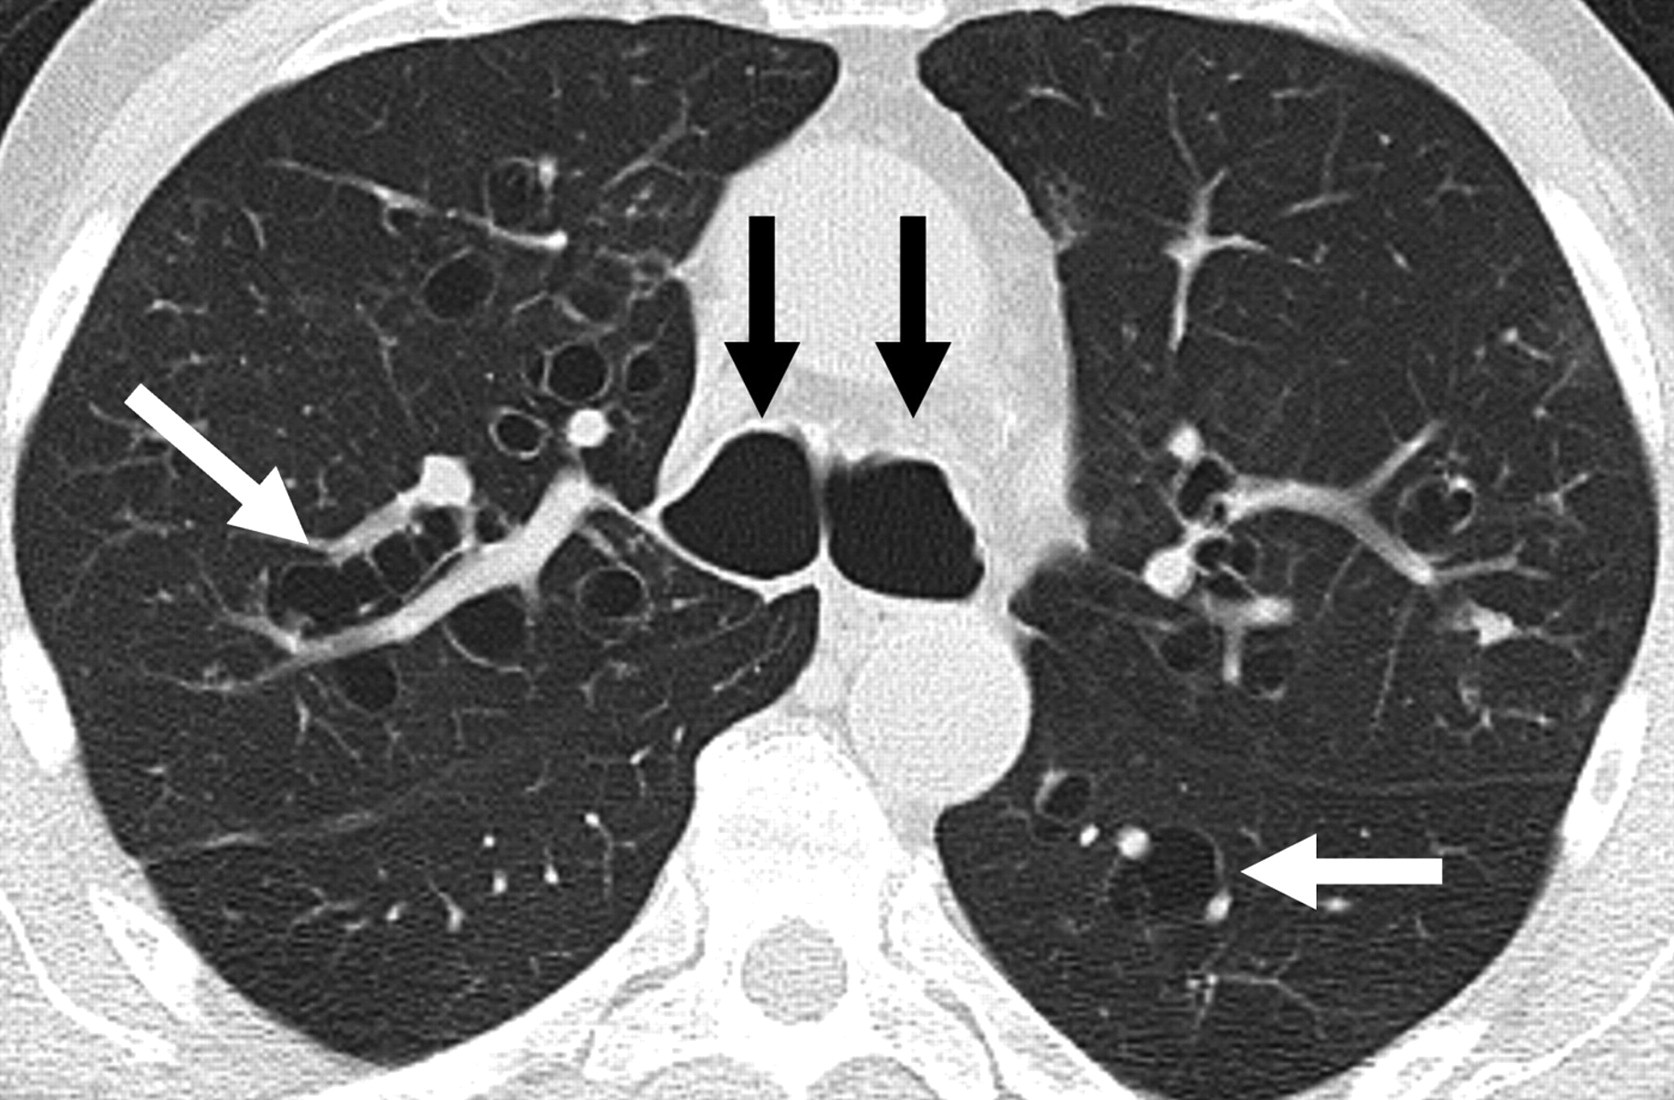

Imaging

HRCT — investigation of choice

| Sign | Finding | Significance |

|---|---|---|

| Tram-track sign | Parallel thickened bronchial walls, uniform calibre, no tapering | Cylindrical bronchiectasis |

| Signet ring sign | Broncho-arterial ratio >1.5 — dilated bronchus beside normal artery | Diagnostic of bronchiectasis |

| Cluster of grapes | Dilated cystic bronchi to pleural surface with air-fluid levels | Severe cystic/saccular disease |

| Other | Mucoid impaction, air-trapping, mosaic perfusion | Functional obstruction |

Reid classification: Three morphological types in increasing severity — cylindrical (tubular), varicose, and cystic/saccular.